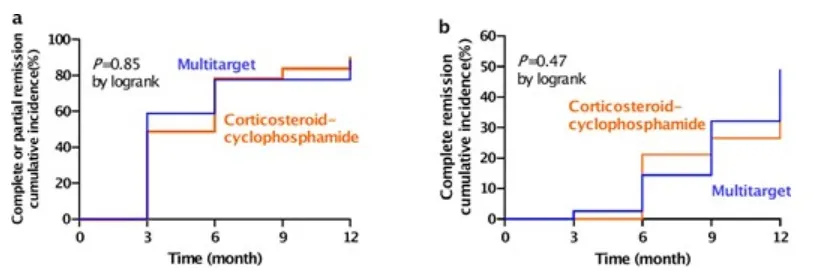

O desfecho primário de remissão completa ou parcial em 12 meses foi alcançado em 31/39 pacientes (79%) no grupo de terapia multitarget e 34/39 (87%) no grupo Ponticelli (RR 0,93; IC 95% 0,72– 1,21; P = 0,85), figura 1A.

A remissão completa em 12 meses foi alcançada por 16 pacientes (41%) no grupo de terapia multitarget e 14 (36%) no grupo corticosteróide-ciclofosfamida, figura 1B.